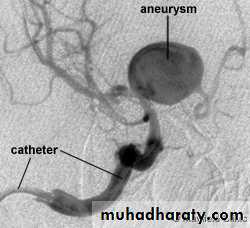

• Angiography

Angiography: